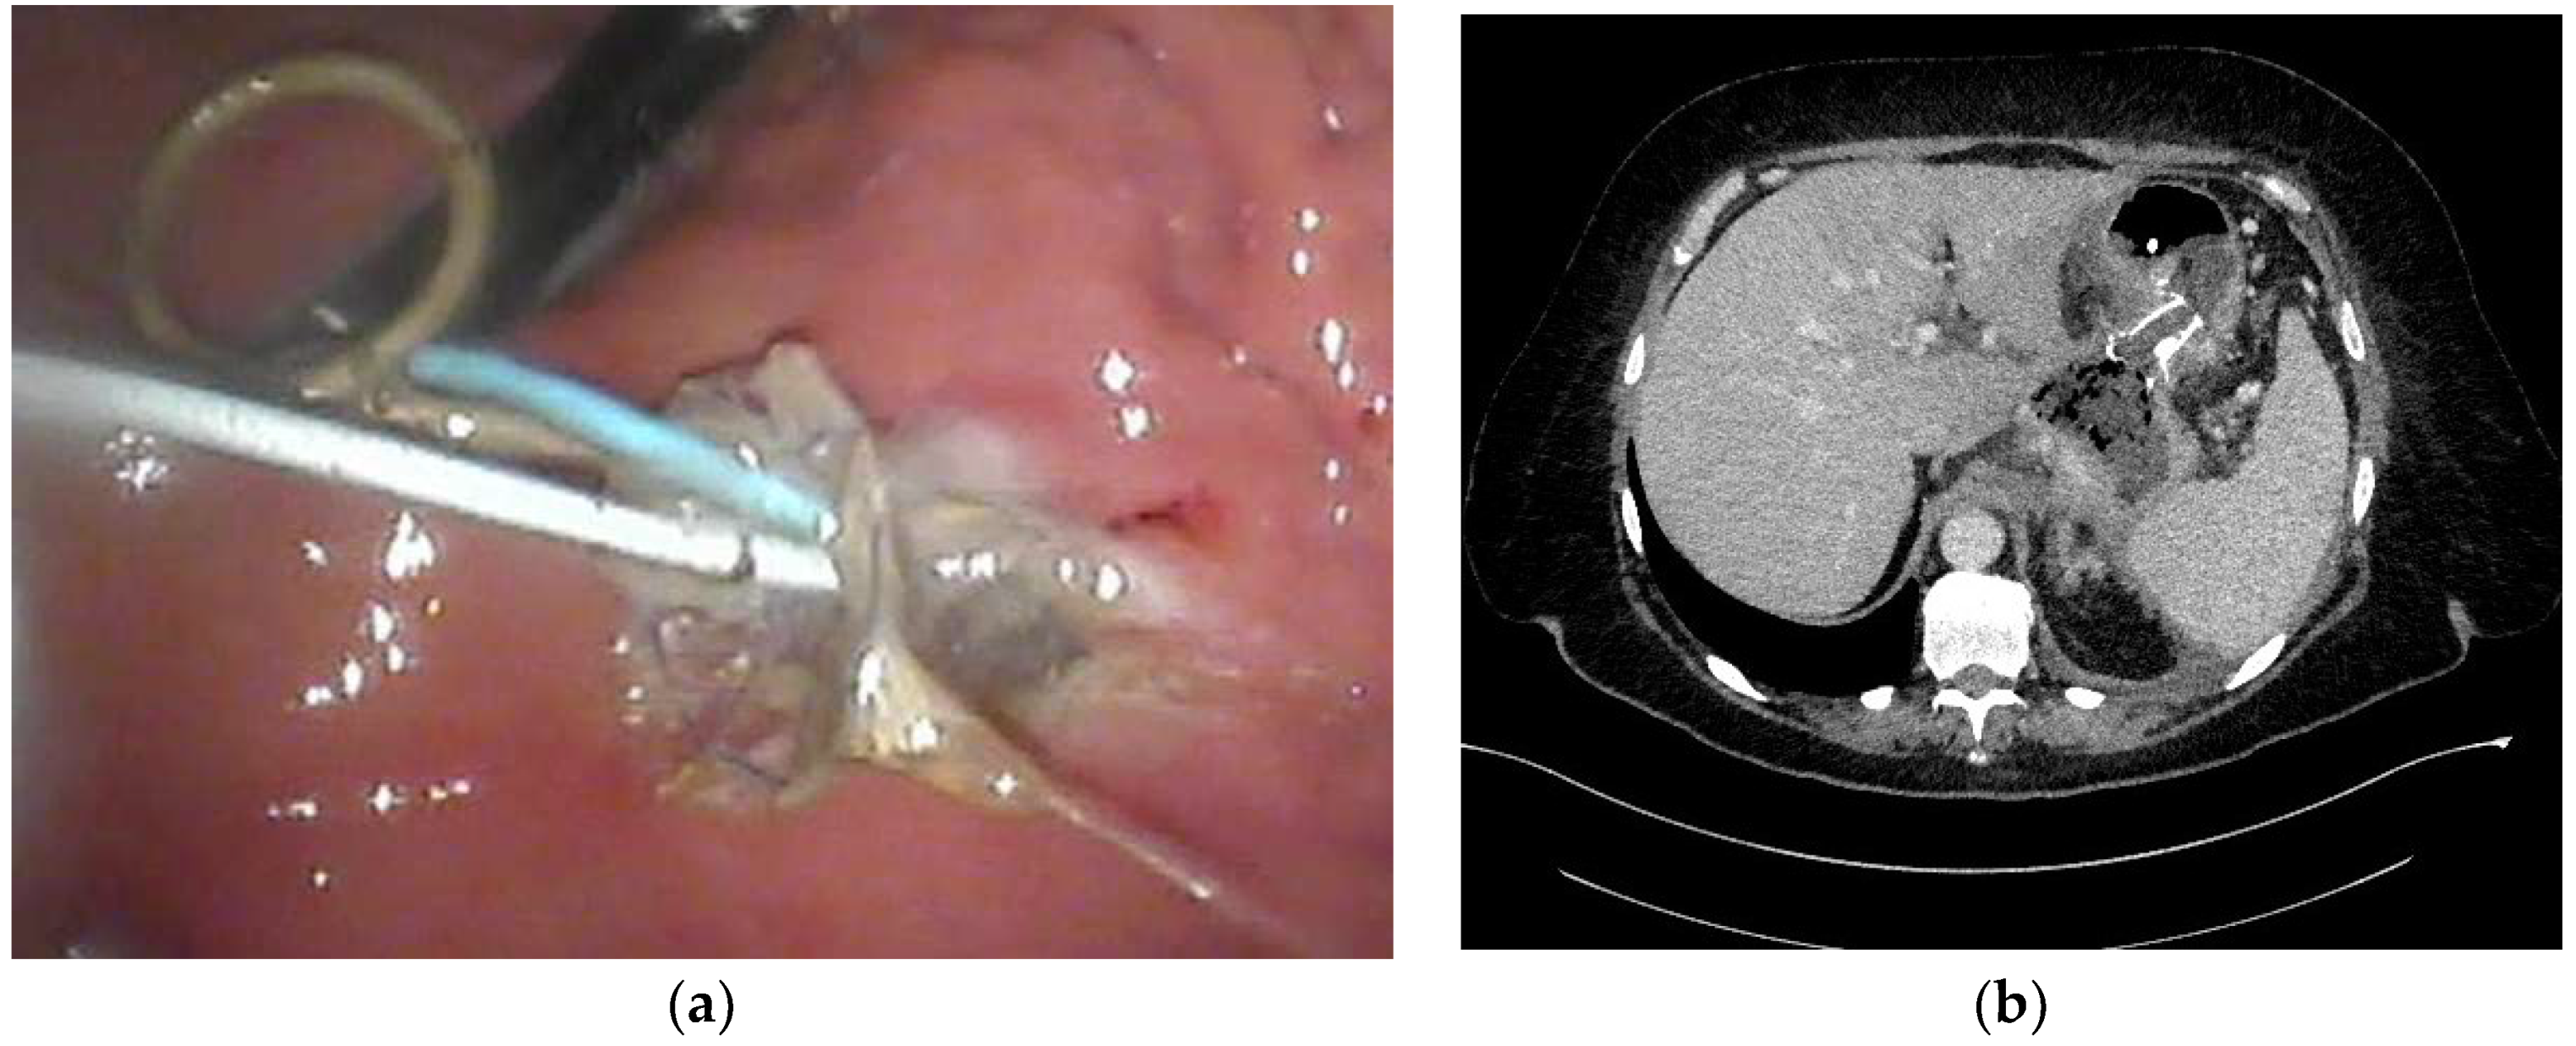

| Endoscopic necrosectomy under fluoroscopic guidance (endoscopic debridement) | Procedure that enable to remove necrotic tissues from necrotic cavity through transmural fistula under fluoroscopy with use of various types of endoscopic tools. Indication for endoscopic debridement is WOPN containing poorly-liquefied necrotic tissues. |

| Direct endoscopic necrosectomy | Procedure accomplished via insertion of endoscope through the transmural fistula into the lumen of WOPN and direct removal of necrotic tissues under endoscopic view with use of different types of endoscopic tools. Direct endoscopic necrosectomy is usually technically easier to proceed during transmural drainage with use of SEMSs. Indications for direct endoscopic necrosectomy are extensive WOPN containing poorly-liquefied necrotic tissues without clinical improvement despite active transmural drainage. |

| Percutaneous drainage | Drainage enables to insert a drain transperitoneally or retroperitoneally into the lumen of necrotic cavity under control of ultrasonography or computed tomography and to flush the necrosis with saline solution through the percutaneous drain. This technique may be used as the only way to approach the necrosis or as additional approach (according to ‘step-up approach’ strategy). |